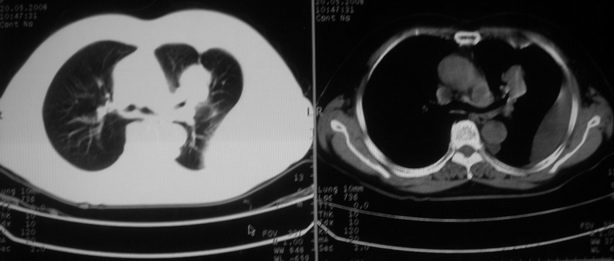

以下是引用w_jianhua在2008-5-22 12:59:00的发言:[br]1.左肺上叶肺癌并左侧胸腔积液可能性大。2不除外支气管内膜结核并包裹性胸腔积液,建议支气管镜检3.左肺下叶肺大泡,肺气肿